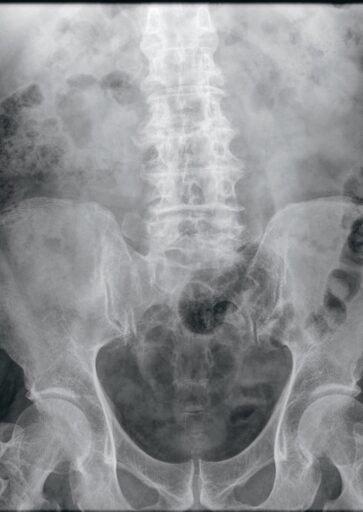

L’abdomen sans préparationUn examen de débrouillage bien utile

Constipation, douleur abdominale, colique néphrétique, ou encore recherche de corps étrangers… Les indications de la radiographie de l’abdomen sans préparation demeurent encore nombreuses, notamment dans le cadre de l’urgence. À l’ère du scanner, du Pet-Scan, de l’IRM et autres examens d’imagerie sophistiquée, les bonnes vieilles méthodes ont un glorieux passé